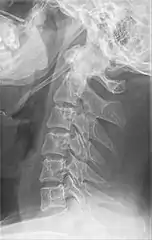

Radiograph, lateral view showing joint-like formation in ossified stylohyoid ligament

Imaging is important and is diagnostic. Visualizing the styloid process on a CT scan with 3D reconstruction is the suggested imaging technique.[11] The enlarged styloid may be visible on an orthopantogram or a lateral soft tissue X ray of the neck.